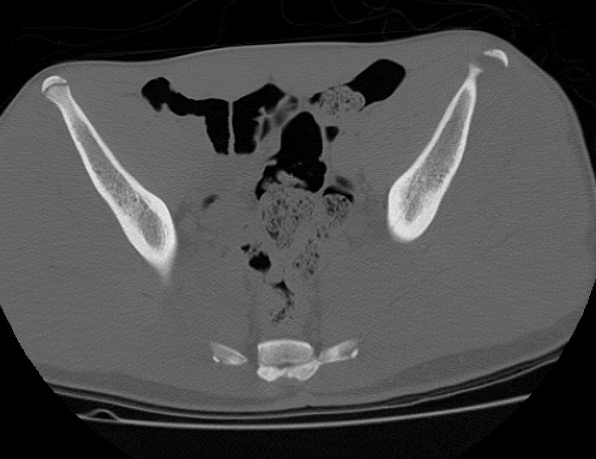

ASIS Avulsion

Attachments

Sartorius & Tensor fascia lata

Imaging

ASIS CT 1ASIS CT 2ASIS CT 3